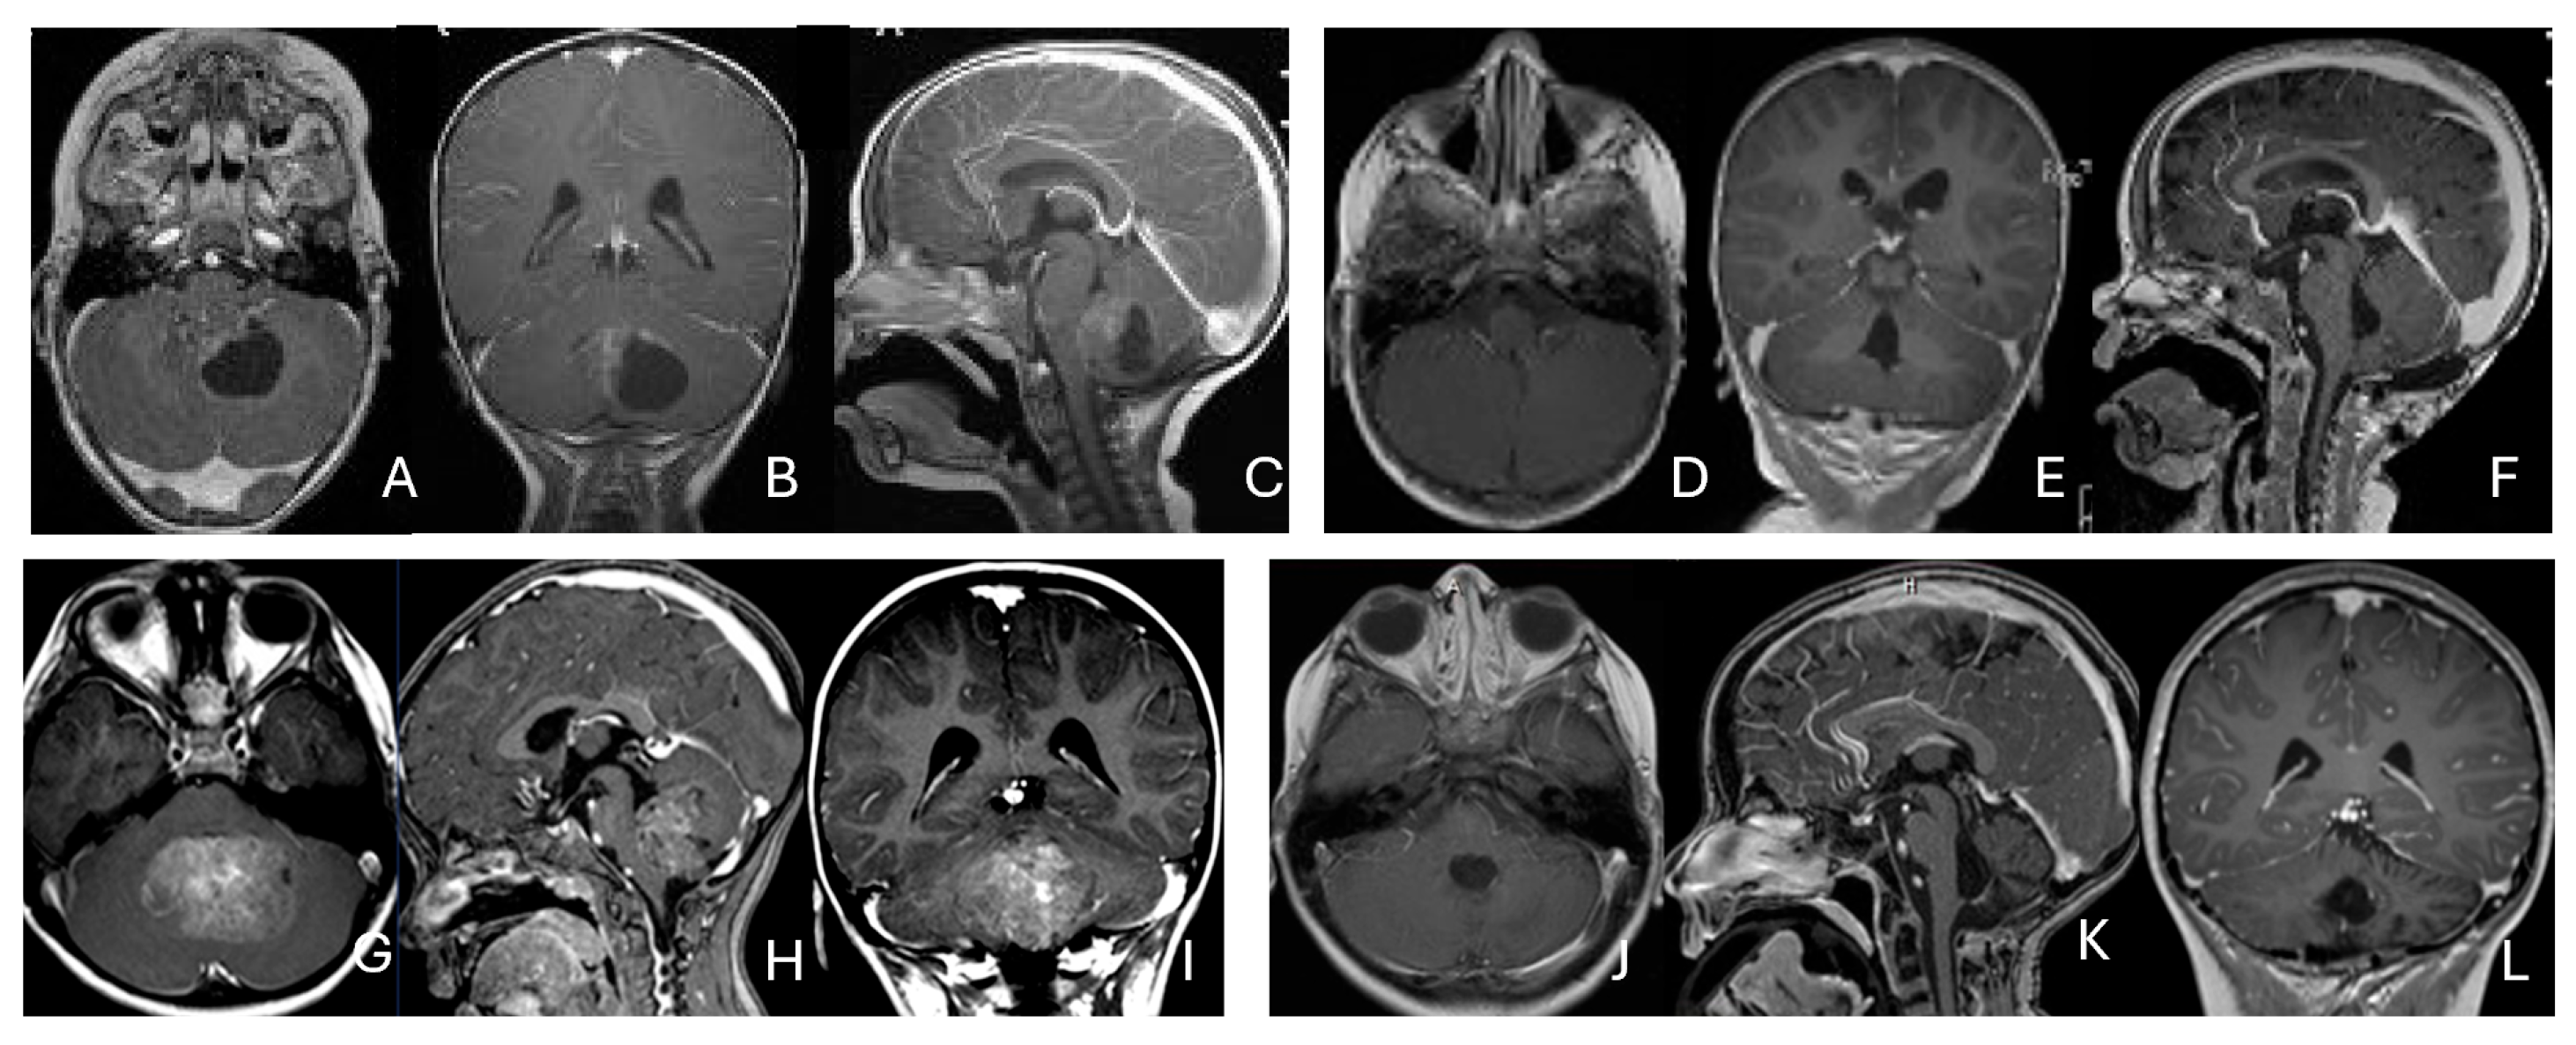

Three tumors were predominantly located within the ventricle, two within the lateral ventricle and another within the third ventricle (Figure 4). None appeared to arise from the choroid plexus or as pedunculated lesions from the ependymal layer; rather, operative and imaging features supported a paraventricular origin because of diffuse attachment to the ventricular wall. Two large hemorrhagic hemispheric tumors extended into the lateral ventricle. These paraventricular ATRT extends into the lateral ventricle (Figure 5).

Figure 4.

Intraventricular ATRT. (A–D): A 7-month-old boy with ATRT within the left lateral ventricle with associated hydrocephalus shown on MR images ((A), axial; (B), coronal; (C), sagittal). Note irregular peritumoral cysts and ependymal invasion which was confirmed at surgery. Postoperative MR image ((D), axial) shows a gross-total resection. The patient had a history of rhabdoid tumor predisposition syndrome. (E–H): A 34-month-old boy with MR images ((E), axial; (F), coronal; (G), sagittal) showing an intraventricular mass at the anterior horn based on the septum pellucidum. ATRT was originated at the junction of the septum pellucidum. Post-contrast MR ((H), axial) confirms resection. (I–L): Post-contrast MR images ((I), axial; (J), coronal; (K), sagittal) of a 3.5-year-old boy demonstrate a large, enhancing third ventricular ATRT with partial extension into the lateral ventricle. The lesion was removed via an interhemispheric transcallosal approach ((L), sagittal).

Figure 5.

Paraventricular ATRT with ventricular extension. (A–D): A 3-month-old girl who presented with emesis followed by acute decerebrate posturing. Post-contrast MR images ((A), axial; (B), coronal; (C), sagittal) reveal a large hemorrhagic mass in a deep centrencephalic location. Postoperative MR ((D), axial) shows a focal dilation of the lateral ventricle after subtotal resection of a parietal para-ventricular ATRT.

Three patients presented with massive subdural/parenchymal masses involving both cerebral hemispheres across the falx cerebri; two bi-frontal and one in bi-occipital (Figure 6). These tumors appeared to originate within the cerebral hemispheres and permeate or traverse the falx cerebri, resulting in bilateral disease.

Figure 6.

Bi-hemispheric ATRT. (A–E): MR images ((A), axial; (B), coronal; (C), sagittal) of a 4-year-old boy show a bifrontal ATRT crossing the falx cerebri, with heterogeneous enhancement. The corpus callosum is compressed posteriorly. At surgery, left frontal component invades and permeates through the falx with extension into the right subdural space. Postoperative images after bifrontal craniotomy ((D), axial; (E), coronal) show tumor resection. Bi-occipital hemispheric ATRT. (F–J): MR images ((F,G), axial; (H), coronal) of a reveal a 22-month-old girl large, inhomogeneous left occipital lobe mass crossing the midline into the right occipital lobe. The lesion invades the posterior falx cerebri and extends into the medial occipital lobe of the right side. A highly vascular tumor was resected via a left occipital craniotomy; the right occipital component was not removed with concern of blindness due to preexisting right homonymous hemianopia. She received chemoradiation with durable disease resolution for over 15 years, as shown on follow-up post-contrast MR ((I), axial; (J), coronal).

Five patients had tumors centered within the fourth ventricle; in four of these, the tumor involved the floor of the ventricle (brainstem) (Figure 7).

Figure 7.

Fourth ventricle ATRT. (A–F): MR images ((A), axial; (B), coronal; (C), sagittal) of a 21-month-old boy show a predominantly cystic fourth ventricular mass. The lesion appeared to arise from the inferior vermis, and the floor of the fourth ventricle was partially infiltrated. Postoperative images ((D), axial; (E), coronal; (F), sagittal) demonstrate gross-total resection. (G–L): MR images ((G), axial; (H), sagittal; (I), coronal) of a 3.5-year-old girl reveal a solid fourth ventricular tumor with heterogeneous enhancement. The floor of the fourth ventricle was intact, and the lesion appeared to originate from the inferior vermis. Postoperative images ((J), axial; (K), sagittal; (L), coronal) confirm gross-total resection.

In five additional patients, tumors straddled both the fourth ventricle, the lateral recess and in some further the CPA and/or the cerebellomedullary fissure (CMF), producing a dumbbell-shaped configuration (Figure 8).

Figure 8.

Fourth ventricle-lateral recess/CMFOK ATRT. (A–E): MR images ((A), axial; (B), coronal; (C), sagittal) of a 12-month-old boy show a fourth ventricular ATRT extending to the CMF through the lateral recess and with multiple peritumoral cysts. A partial invasion to the pons was noted at surgery. Postoperative images ((D), axial; (E), sagittal) demonstrate gross-total resection. Fourth ventricle-CPA ATRT. (F–J): MRI ((F): axial T2-weighted; (G): post-contrast coronal; (H): post-contrast sagittal) of a 5-month-old girl reveal a heterogeneous, dumbbell-shaped ATRT extending from the fourth ventricle into the CPA/CMF. During surgery, invasion of the lateral wall of the medulla oblongata was observed, and a subtotal resection was achieved. Post-contrast MRI ((I): axial; (J): sagittal) reveals residual enhancing tumor at the CMF.

Eight patients had lesions localized to the CPA/CMF region (Figure 9). Among them, two had concurrent bilateral lesions. In one bilateral case, the lesions were asymmetric with questionable evidence of spinal cerebrospinal fluid dissemination, whereas another patient exhibited symmetric bilateral lesions.

Figure 9.

Cerebellopontine angle (CPA) ATRT. (A–E): T2-weighted MR images ((A), axial; (B), coronal) of a 7-week-old girl show a massive ATRT centered in the right CPA/CMF. Postoperative MR images ((C), axial; (D), coronal) show a gross-total resection of a highly vascular, necrotic mass. Intraoperative photograph following tumor resection illustrates key landmarks: LR, lateral recess; V, trigeminal nerve; VII/VIII, facial and vestibulocochlear nerves; IX/X, glossopharyngeal and vagus nerves. The cranial nerves were free of tumor. ATRT appeared to originate from the lateral posterior cerebellar lobe. (F–K): MR images ((F), axial; (G), axial) of a 3.5-year-old girl show bilateral CPA tumors: a larger, partially cystic mass on the left (open arrow) and a smaller solid mass extending toward Meckel’s cave on the right (solid arrow). The left-sided tumor was resected via a retrosigmoid approach ((H), axial; (I), axial). The lesion arose from the lateral cerebellar hemisphere and extended into the CPA cistern without cranial nerve invasion. Following chemoradiotherapy, the right-sided lesion resolved ((J), axial; (K), axial).

None of the CPA ATRTs showed evidence of cranial nerve origin at the time of surgical inspection (Figure 9E).